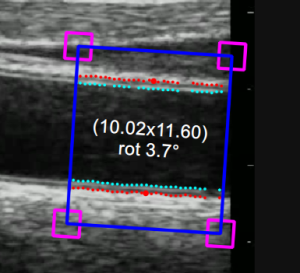

T he B-mode Region of Interest (ROI) is the portion of the image where both the diameter and the IMT are calculated. The points of the Lumen-Intima interface and the Media-Adventitia interface are displayed within the ROI in cyan and red color respectively. The ROI can be moved, resized, and/or rotated. Each time you change the position, size and/or inclination of the ROI, the analysis is re-initialized.

• Click inside the video window and drag until the ROI is complete (the size of the ROI is shown in the Setup panel and graphically within the ROI).